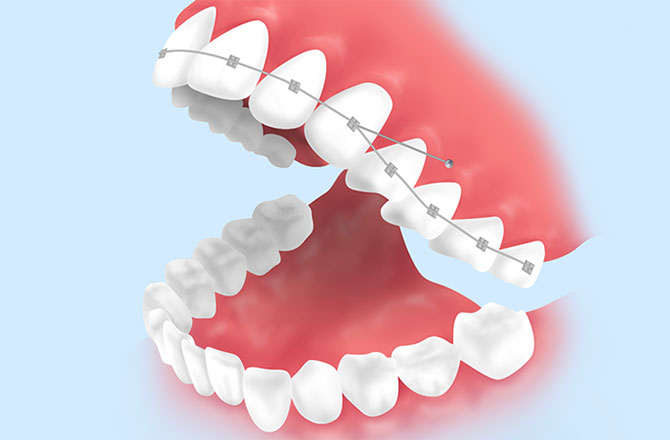

インプラントアンカー

矯正歯科用に開発された小さな器具「アンカースクリュー」を使った矯正治療です。

あごの骨に器具を埋め込み、それを固定源として歯を動かすため、従来の矯正では難しかった方向にも歯を移動させることができます。また、歯を大きく動かせるため、治療期間を短くできるのも特長です。

インプラントアンカーを使用することで、より安全に短期間で矯正治療を行うことが可能です。